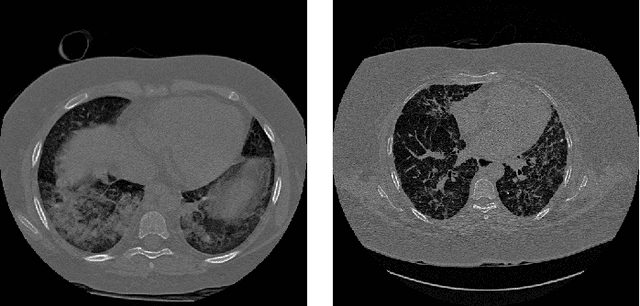

Abstract:Analysis of cancer and other pathological diseases, like the interstitial lung diseases (ILDs), is usually possible through Computed Tomography (CT) scans. To aid this, a preprocessing step of segmentation is performed to reduce the area to be analyzed, segmenting the lungs and removing unimportant regions. Generally, complex methods are developed to extract the lung region, also using hand-made feature extractors to enhance segmentation. With the popularity of deep learning techniques and its automated feature learning, we propose a lung segmentation approach using fully convolutional networks (FCNs) combined with fully connected conditional random fields (CRF), employed in many state-of-the-art segmentation works. Aiming to develop a generalized approach, the publicly available datasets from University Hospitals of Geneva (HUG) and VESSEL12 challenge were studied, including many healthy and pathological CT scans for evaluation. Experiments using the dataset individually, its trained model on the other dataset and a combination of both datasets were employed. Dice scores of $98.67\%\pm0.94\%$ for the HUG-ILD dataset and $99.19\%\pm0.37\%$ for the VESSEL12 dataset were achieved, outperforming works in the former and obtaining similar state-of-the-art results in the latter dataset, showing the capability in using deep learning approaches.